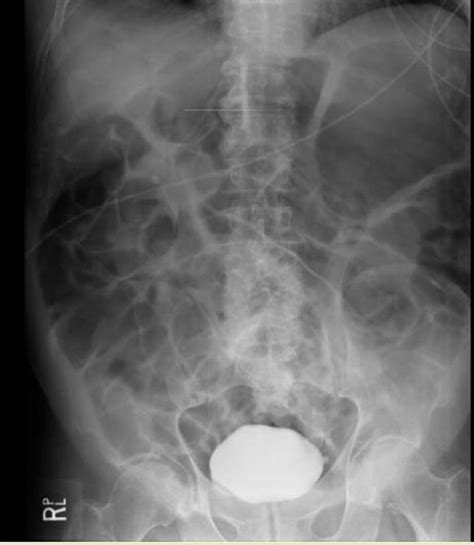

Operation bei gastroenteralem Meteorismus

Operation bei gastroenteralem Meteorismus from www.rinderskript.net

Meteorismus : Magenschmerzen: Ursachen & Hausmittel | Pascoe - Vor diagnostischen untersuchungen im bauchbereich zur reduzierung von gasschatten im röntgenbild;

Vor diagnostischen untersuchungen im bauchbereich zur reduzierung von gasschatten im röntgenbild;